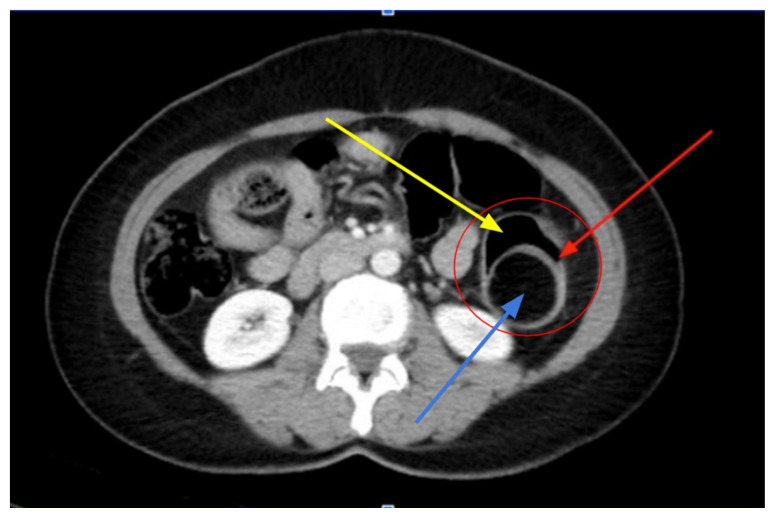

Intussusception is a familiar diagnosis among the pediatric population; however, it is rarely considered among the adult population due to a myriad of life-threatening pathologies within the abdomen. We present an adult female who presented to the emergency department (ED) with abdominal pain and constipation. Laboratory testing and a computed tomography (CT) scan of the abdomen were ordered. Laboratory test results were notable for an elevated lymphocyte count as well as leukocyte esterase, white blood cells (WBC), and bacteria seen on urinalysis. The computed tomography scan detected a colo-colic intussusception secondary to a benign mass within the bowel lumen. The mass was surgically resected and the patient had an uneventful postoperative course. This unique case represents the occurrence of a pathology to which the adult population is not immune, and therefore should not be overlooked when evaluating a non-specific case of abdominal pain.

Topics: Intussusception, colo-colic, obstruction, abdominal pain, constipation, female, mass, bowel, lymphocyte, ultrasound, computed tomography.